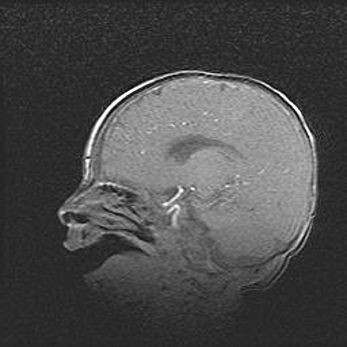

Церебральная ишемия II.

Возраст: 5 дней

Вес: 3400 г

Пол: женский

Окружность головы: 35 см

Срок гестации: 39 недель

Церебральная ишемия – это заболевание, характеризующееся недостаточностью (гипоксией) либо полным прекращением (аноксией) снабжения мозга кислородом по причине закупорки одного или нескольких сосудов. Это приводит к  что метаболическим расстройствам различной степени тяжести в тканях головного мозга, развитию коагуляционных некрозов и гибели нейронов.